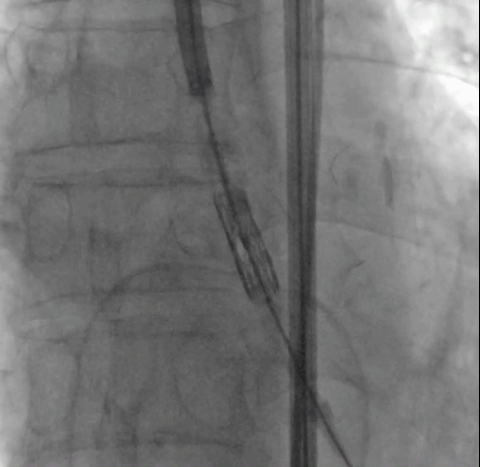

病例3(经颈动脉TAVI)

患者男性,67岁,头晕伴胸闷、胸痛6月余,术前心脏超声提示主动脉瓣增厚钙化伴重度狭窄,峰值流速4.9m/s,峰值压差94mmHg,平均跨瓣压差59mmHg,瓣口面积0.6cm2。CT显示主动脉瓣为Type I型二叶瓣,瓣叶边缘及左右冠瓣融合嵴严重钙化,致瓣口极度细窄。瓣环面积528.8mm2,测算直径25.9mm,左冠脉开口高度14.4mm,右冠脉开口高度17.5mm。患者合并重度肺气肿、多发肺大泡、支气管扩张,肺功能极差,静息状态下氧饱和度仅约80%,STS评分8.6%,属于外科手术高风险患者。

CT重建显示患者双侧髂动脉、股动脉、锁骨下动脉质量极差,多发钙化狭窄伴局部夹层,无法经股动脉和锁骨下动脉入路。而且患者重度肺气肿致心脏两侧受压,心尖被压缩在胸骨及肋弓骨性融合后方,亦无法经心尖入路。评估双侧颈动脉近端均有钙化斑块伴轻度狭窄,平均管径约6mm,左侧管径略大于右侧。颅内Willis环交通支通畅,可以耐受经单侧颈动脉介入手术。

经术前详尽影像学重建、评估及病例讨论,最终决定在脑氧监测下对患者实施经左侧颈总动脉TAVI手术。术中左侧颈总动脉多次预扩后顺利置入血管鞘至升主动脉,跨瓣成功后先以23#球囊预扩,再“0位”植入25# Renatus介入主动脉瓣。手术耗时约2小时,介入主动脉瓣植入位置理想,功能表现良好,主动脉瓣峰值流速及平均跨瓣压差分别降至1.75m/s和5mmHg,造影及TEE观察仅有轻微瓣周漏,无中央型反流。术后左颈总动脉造影无明显狭窄,手术全程脑氧饱和度正常,无传导阻滞、无冠脉异常。

颈动脉评估

瓣膜“0位”释放 术后主动脉根部造影